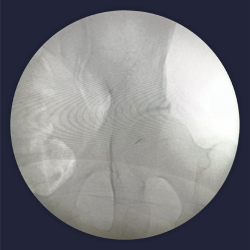

Contrast dye spread of piriformis

image 891

Intra op fluoroscopy images of piriformis injection